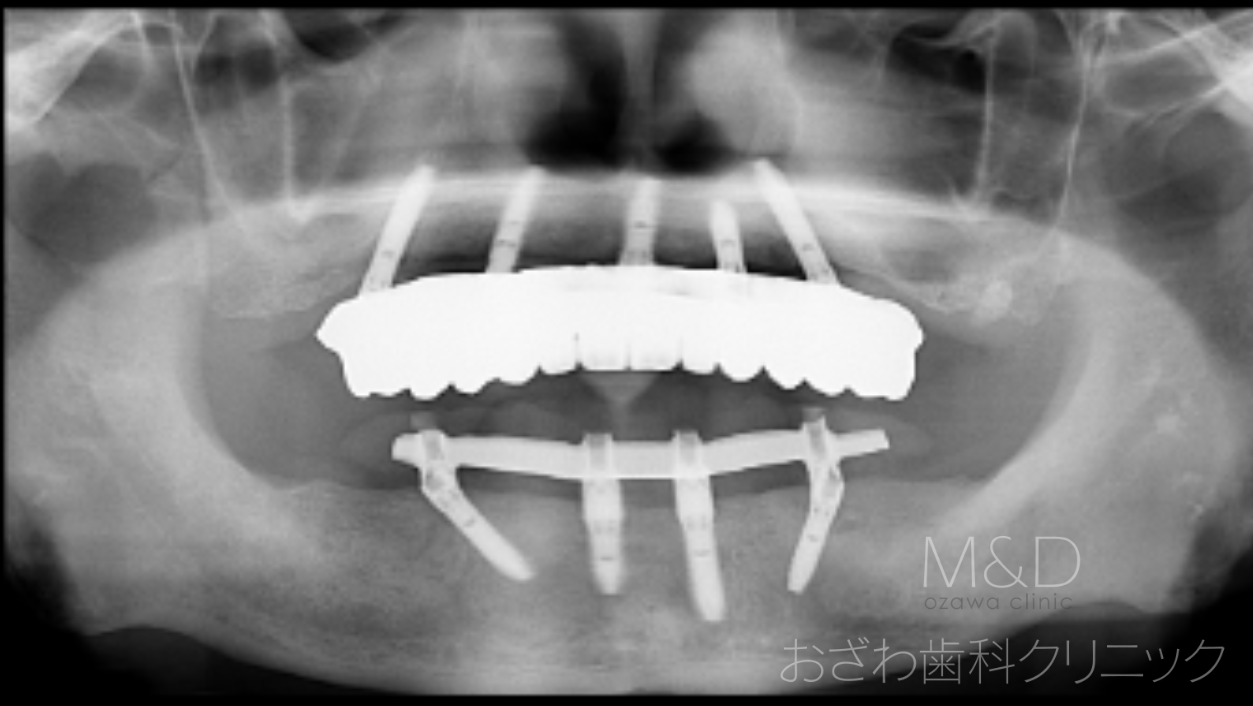

術後

上下顎残存歯の抜歯、上顎5本、下顎4本(オールオン4)インプラント

(上下顎即時負荷:オペの日に仮歯が入ります)

上顎 340万円(税別)フルジルコニアオールセラミック

下顎 250万円(税別)アクリル